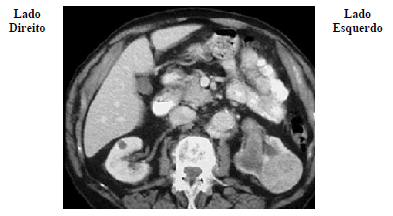

Um paciente de 65 anos de idade compareceu ao urologista por apresentar hematúria macroscópica, emagrecimento de 5 kg em dois meses e dor abdominal. Ao exame físico, o médico encontrou uma massa abdominal palpável em região de flanco esquerdo. Solicitou então uma tomografia computadorizada de abdome, demonstrada nessa imagem.

Com base nesse caso clínico e nos conhecimentos médicos correlatos, julgue o item a seguir.